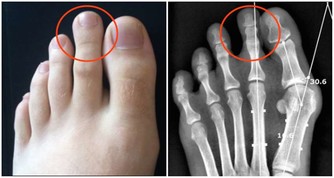

在德克薩斯州旅行結束後,Bill決定要仔細檢查一下自己的肺,畢竟他是一位有著55年菸齡的老煙民。在找到梅奧診所健康系統肺科的Adel Zurob醫生,醫生了解情況後建議Bill做一項肺癌篩查(低劑量CT)。檢查結果顯示:右肺有一個小的癌變結節。通過進一步的正電子發射斷層掃描(PEC-CT),顯示肺部以外沒有擴散或轉移的徵象。醫生建議,立即進行手術治療。

在醫生切除了Bill的癌變病灶後,還為他進行了胸部檢查以確定是否有淋巴結轉移的跡象,並對可疑的淋巴結進行了預防性切除。Zurob醫生說:“Bill的肺癌治癒的可能性極高,對Bill來講,沒有出現任何轉移是再好不過的了。”